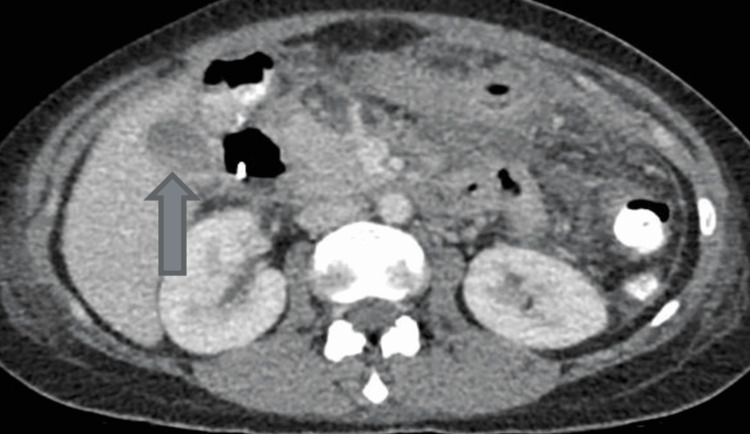

Computerized tomography scan of abdomen and pelvis showed features of acute pancreatitis without any evidence of pancreatic necrosis and thin-walled distended gallbladder containing multiple gallstones. The distal CBD was dilated measuring up to 13 mm with positive double duct sign (moderate intra- and extra-hepatic duct dilatation and mild pancreatic duct dilatation) as shown in Figures 1–3.